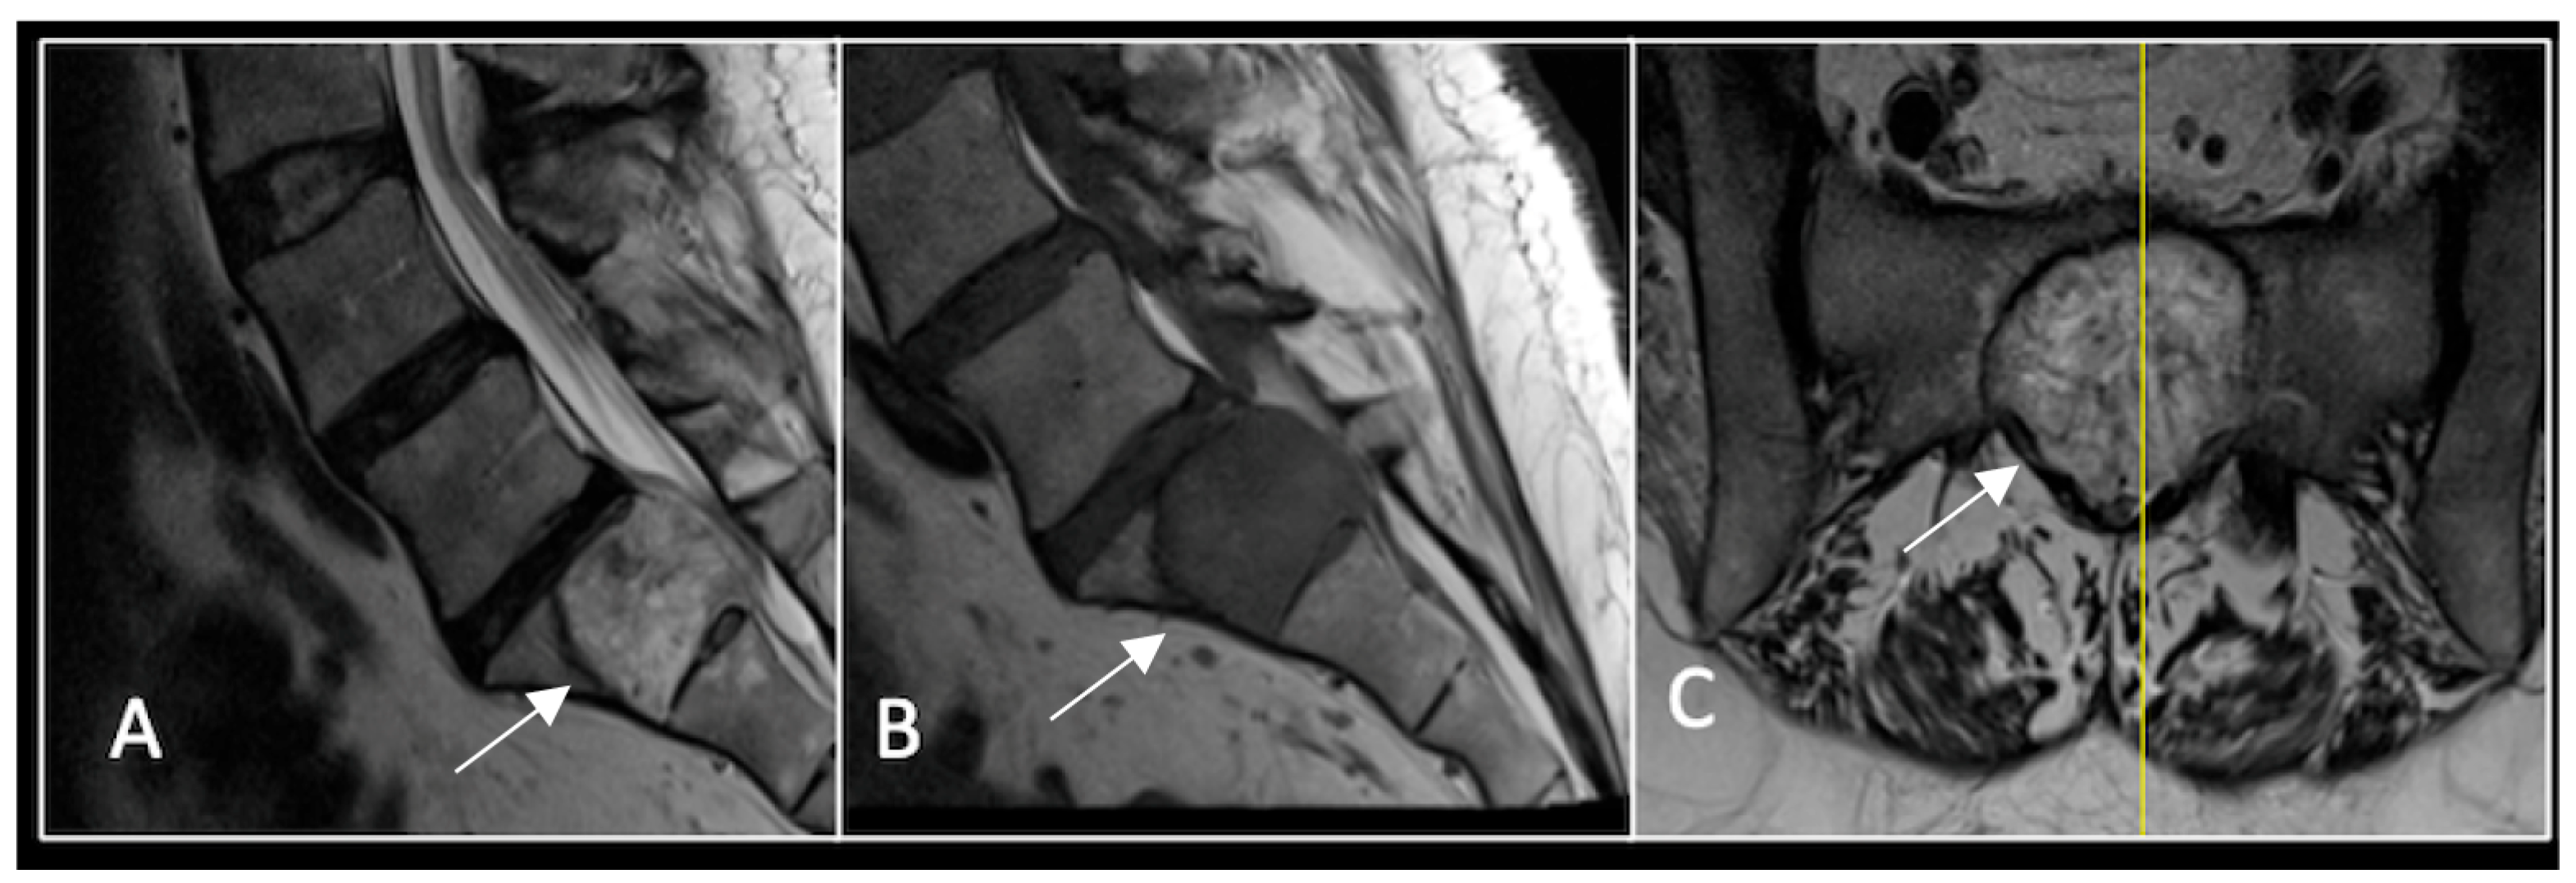

This 63-year-old male presented with sacral pain and right-sided S1 radiculopathy. He was subsequently referred to our institution after diagnostic imaging revealed a destructive lesion within the S1 vertebra (Figure 4). The patient developed symptoms of acute cauda equina syndrome, for which we recommended an emergent surgical decompression to be performed at the referring hospital. Biopsy confirmed a conventional chordoma. The patient chose to undergo separation surgery, given the significant morbidity associated with an en-bloc sacral resection, including sacrifice of the neural structures innervating his bladder and bowel. He received adjuvant proton beam therapy, and 6-monthly surveillance imaging revealed stable disease (Figure 5). Unfortunately, 12 months post-separation surgery, there was evidence of tumour progression with epidural extension and symptomatic deterioration in bladder function, requiring revision surgical debulking (Figure 6).

Figure 5.

MRI imaging following separation surgery. (A) T2W sagittal; (B) T1W sagittal; (C) T2W axial. Imaging shows removal of posterior lumbosacral elements with residual disease (arrow) within the S1 vertebral body but significant reduction in tumour dimensions. The yellow line on the sagittal images indicates the level at which the axial image was obtained.